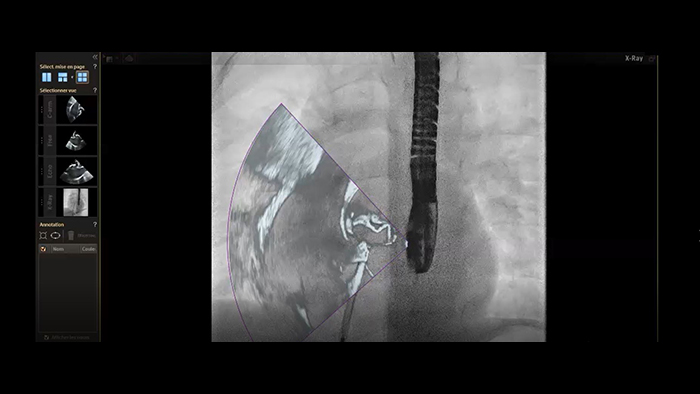

Anatomical landing zone marking on TSM Pro

SmartCT live guidance

Aortic coarctation stenting guidance with VesselNavigator